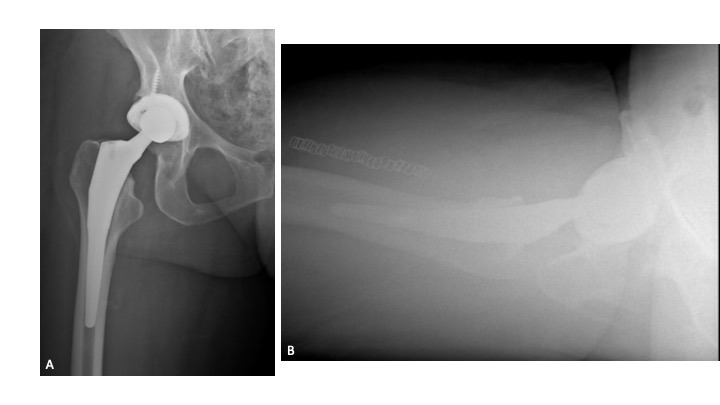

Twelve-weeks following re-implantation (2018), the patient experienced recurrent THA instability and was transitioned to our care for definitive treatment. At this time, the patient had a BMI of 24.22 kg/m2 and a past medical history of hypertension, rheumatoid arthritis, gastroparesis, hypothyroidism, and iron deficiency anemia. Relevant prescription medications included calcium carbonate, cholecalciferol, cyclobenzaprine, diltiazem, gabapentin, levothyroxine, and lisinopril. In August 2018, the patient underwent right THA acetabular revision with a porous titanium acetabular shell (56-mm) and dual mobility acetabular liner (44-mm), with four screws (30-mm x 2; 25-mm x 2) for adjuvant fixation. The existing stem was well-fixed and left in place, and a 44-mm/28-mm (+6) ceramic taper sleeve head was impacted. (Figures 4a-b) The patient followed a normal post-operative course and was ambulating pain free without assistance.